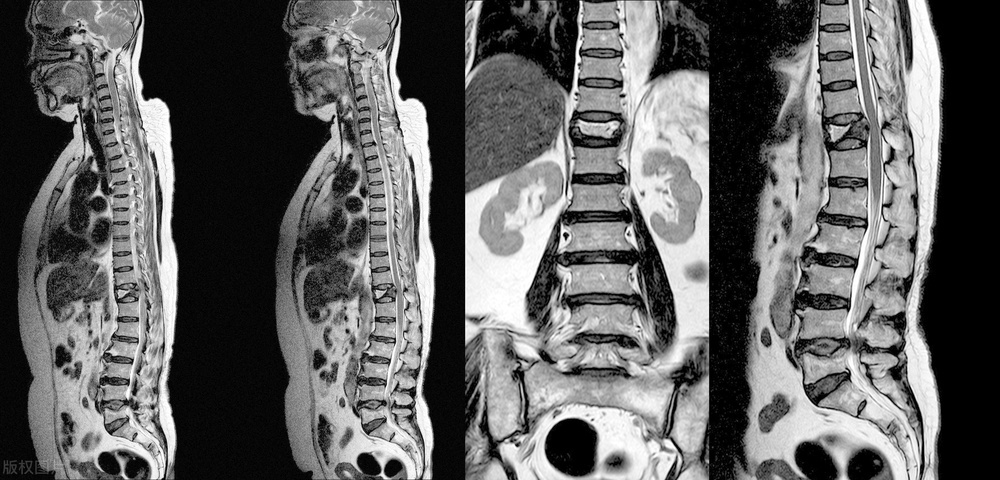

检查出腰椎间盘轻度膨出,没有症状需要治疗吗

一 位 2 9 岁的女性线上咨询,说检查出来自己 腰 4- 5 和 腰5骶1 椎间盘轻度膨出。之前没有什么症状,但自从检查出来后,心里总是很担心,感觉腰也开始酸了。

通过跟患者的沟通,我告诉她目前不用治疗,只需要做两件事,第一件事就是放松心情,不要太担心,不要总觉得自己腰椎出了多大问题,但要多注意对腰部的保养;第二件事就是纠正自己很多不良习惯,避免久坐久站的工作状态,学会自己调节,时间久了站起来活动活动,休息时间多锻炼腰背肌,积极面对就好了。